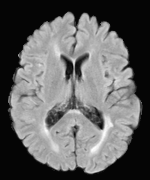

Patch size is another important parameter of the network. In computer vision applications such as object detection, usually a whole 2D image is used as a feature. However, full 3D medical images can not typically be used because of memory limitations. Fig. 4 shows examples of lesion memberships obtained with different sized 2D patches. As the patch sizes increases, the false positives that are mostly observed in the cortex tend to decrease. Fig. 5 shows a plot of Dice and LFPR with various patch sizes, ordered from left to right according to their increasing size. Note that smaller patches ( to ) produced significantly lower Dice and higher LFPR compared to other patches (), as seen from the memberships in Fig. 4. Also some of the highest Dice and lowest LFPR were observed for patches with large in-plane size, i.e., , , and . It was observed in Fig. 5 that there is no significant difference between Dice coefficients for , , or , but LFPR of both and are significantly lower than that of (). We chose as the optimal patch size. Other choices of smaller and patches (not shown) yielded worse results. Note that although training was performed with different patch sizes, the memberships were generated slice by slice, as the trained model consisted only of convolutions and did not need any information about patch sizes.

In our experiments, we used large 2D patches similar to Ghafoorian et al. (2017b), in comparison to isotropic 3D patches as used before, e.g., in Valverde et al. (2017), in Wachinger et al. (2017), and in Kamnitsas et al. (2017). The rationale behind using large anisotropic patches is twofold. First, experiments with full 3D isotropic or patches showed little or no improvement in Dice and led to increased false positives, with memberships similar to the one with patches, as shown in Fig. 4. Larger isotropic patches, e.g. or , showed inferior segmentation, and in some cases, optimization did not converge. The reason is that the FLAIR images in the test datasets had inherently low resolution in the inferior-superior direction, mm and mm compared to in-plane resolution of mm. Therefore 2D axial patches capture the high resolution in-plane information that represents the original thick axial slices. Second, the lesions are usually focal and small in size, unlike other brain structures. Therefore a very large isotropic patch around a small lesion can include superfluous information about the lesion, which can increase the amount of false positives. Note that with in more recent studies employing high resolution 3D FLAIR sequences, it is trivial to extend the algorithm to accommodate for 3D patches.